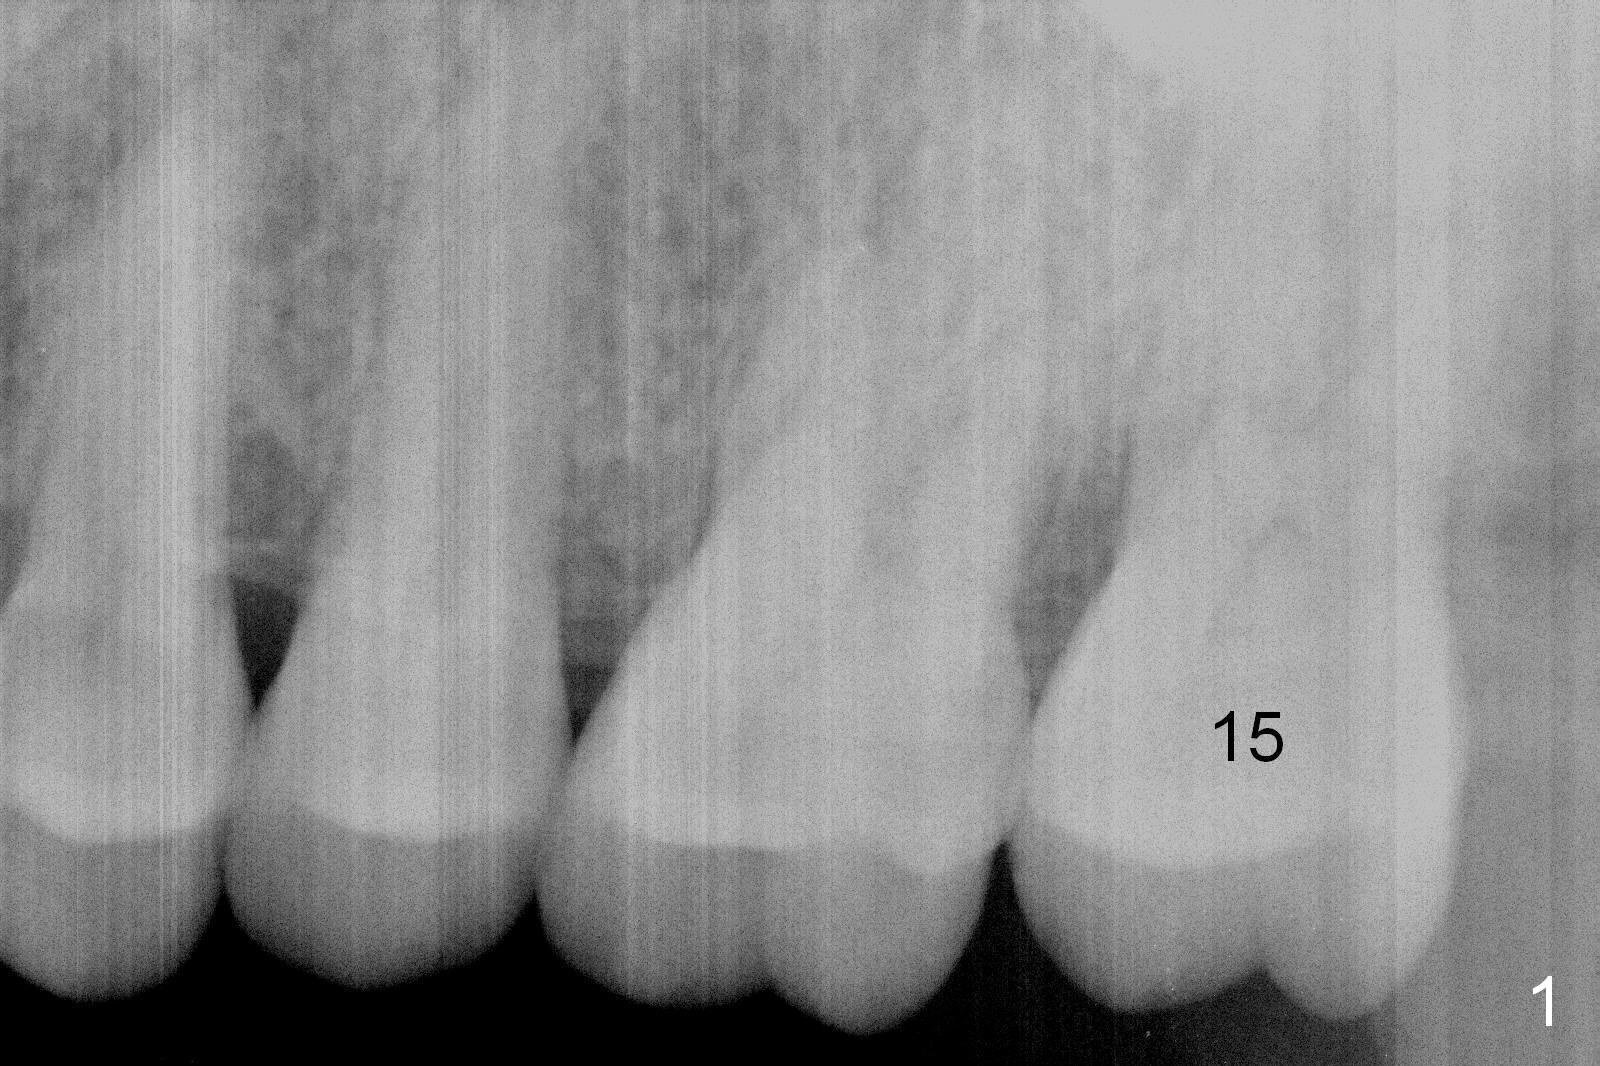

A 50-year-old man (TK) had sign & symptom of crack tooth at #15 (Fig.1) and chose to have root canal therapy done by a specialist. One month later, he returns for crown; exam reveals a crack line mesiodistally (Fig.2). The patient agrees to have immediate implant (Fig.3 design: 6x14 mm). The buccal roots fracture upon luxation. Osteotomy starts in the septum with a 2 mm pilot drill and deviates to the palatal socket, followed by 2, 3, 4 mm tapered osteotomes. A series of taps are placed: 6x17 mm one achieves stability (Fig.4). When the latter is removed, there is no sign of sinus air leakage. A 6x14 mm implant (Fig.5 I) and a 5x3 mm abutment (A) are placed. After abutment height adjustment, an immediate provisional is fabricated. Allograft with Osteogen is placed in the remaining sockets and gaps (Fig.6 *). Fig.7 shows the inner side of the provisional with double arrows indicating the dimension of the abutment, whereas arrowheads the dimension of the socket buccopalatally. When the provisional is cemented (Fig.8 P), it completely seals the socket. As long as the provisional stays, bone graft will not be lost.